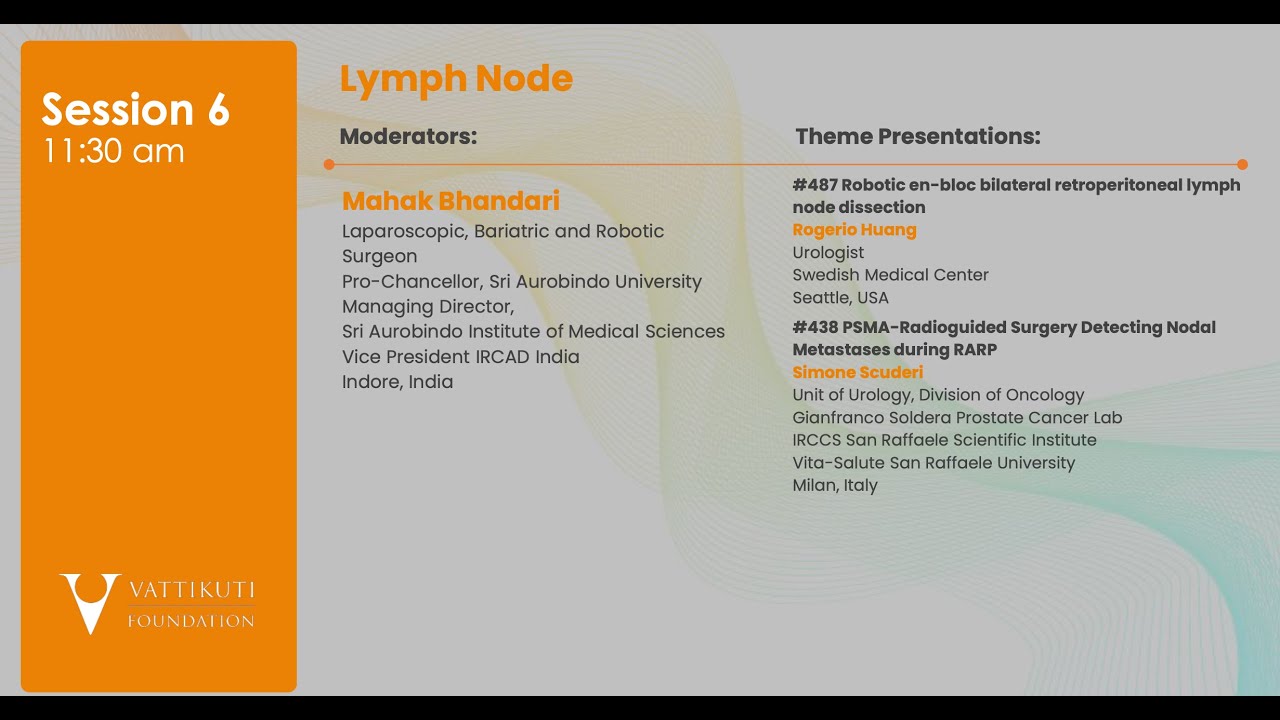

Jaipur Saturday Session 6 Lymph Node

Humans of Robotic Surgery, KS Awards, Robotics, Surgeon, Video Library ';